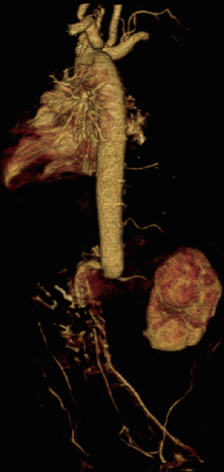

入院诊断:新生儿缺氧缺血性脑病、胎粪吸入性肺炎、新生儿低血糖症、巨大儿。患儿入院后予苯巴比妥止惊、抗感染、营养心肌、营养神经等对症支持治疗。入院第3天患儿抽搐止,双上肢肢端肤色红润、皮温正常、CRT正常,双下肢肢端肤色苍白、皮温低、CRT 延长,双上肢血压高于双下肢,血压差异超过 20 mmHg。予行心脏彩超查:左、右室心肌肥厚, 左室流出道梗阻, 卵圆孔未闭。 腹主动脉超声检查:腹主动脉近肾动脉水平内可见实质性低回声充填,内未见明显血流信号,双侧髂外动脉血流速度约15cm/s, 呈阻塞性频谱。进一步头颅及腹部增强 CT 示: 头颅未见明显异常;左肾动脉平面以下腹主动脉、髂总动脉未见显影,考虑为动脉栓塞可能;主动脉弓远端轻度缩窄;主动脉弓远端囊样突出,不除外弓动脉残留并附壁血栓形成;室间隔及左右室壁心肌肥厚;左肾血灌注减低,不除外左肾动脉受累狭窄。